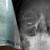

Лекарите отстраниха метална сачма от орбитата на дясното око при спешна операция

При спешния офталмологичен преглед лекарите установили метално чуждо тяло в орбитата на дясното око, както и разкъсана рана на клепача, съответстваща на входно отвърстие от прострелване. Зрението на пациента към момента на приемането било силно намалено - до броене на пръсти пред окото.

След пълни изследвания и подготовка, екипът на доц. Яни Здравков извършил спешна хирургична интервенция, при която успешно отстранил металното чуждо тяло - сачма от въздушна (газова) пушка.